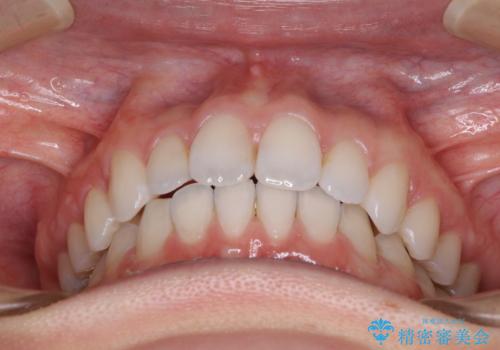

深い咬み合わせと奥歯のむし歯 総合歯科治療

矯正治療後は、奥歯の虫歯や銀歯を補綴・修復治療することとしました。

上顎歯列を下顎に対して4mmほど移動させる必要があったため、治療は長期化することが予想されましたが、患者様にはこちらの期待以上にゴムかけなどに協力いただき、補綴治療も含めて2年強で終えることができました。